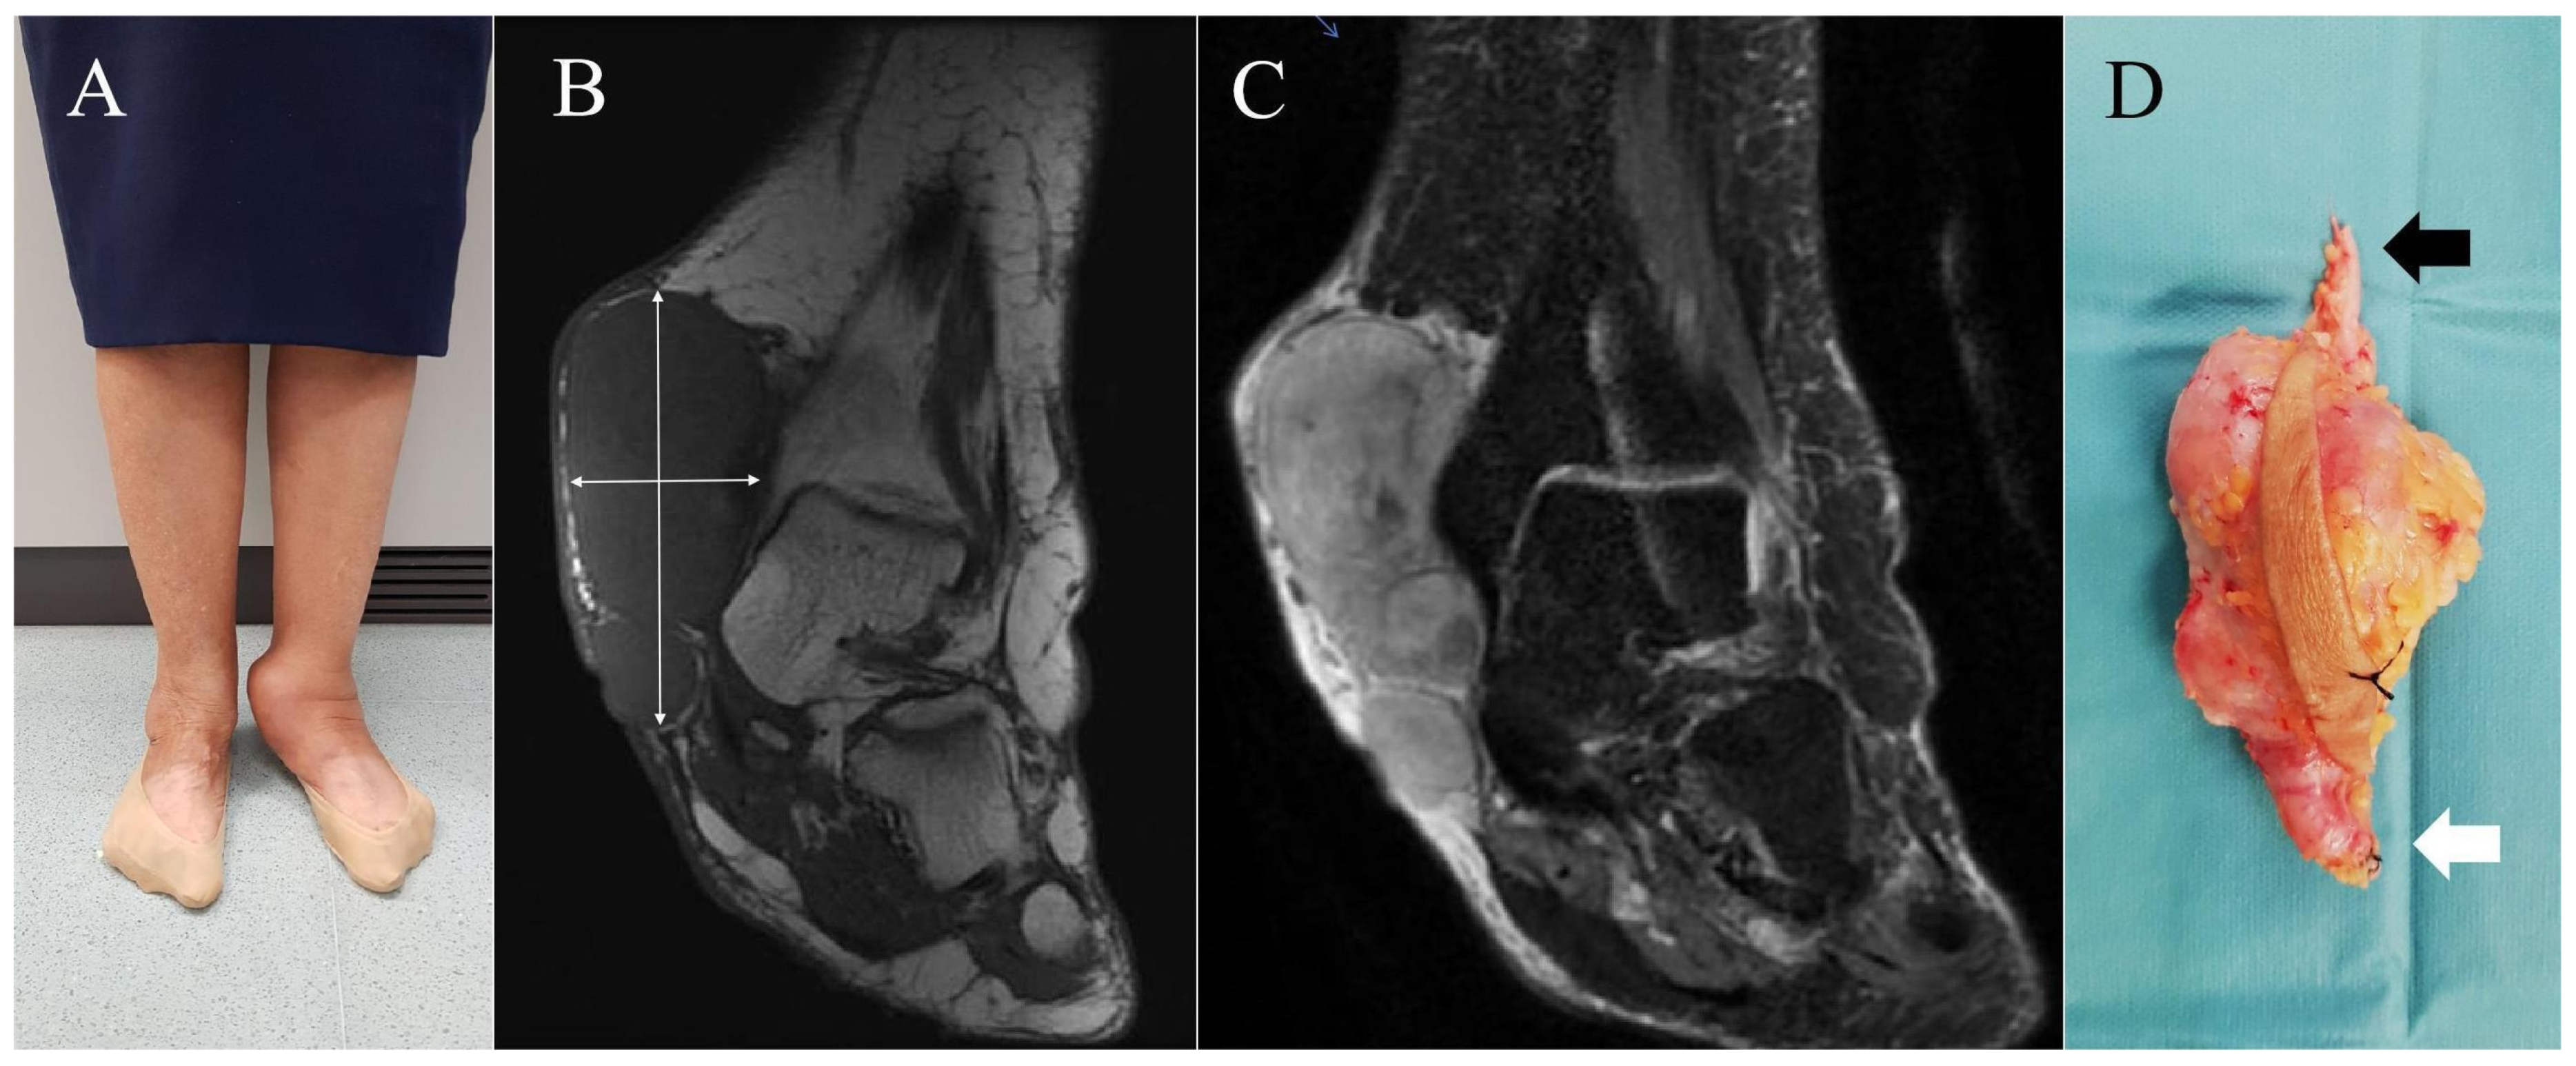

All patients were surgically treated either as primary tumours or by widening the surgical margins of a previous unplanned resection according to well-established oncological principles [33,34,35,36]. In patients treated as primary cases, wide excision was performed with lateral and superficial margins of at least 2 cm from the lateral and superficial edges of the tumor. The great saphenous vein was systematically identified and ligated both proximally and distally at a minimum distance of 2 cm from the tumor edges (Figure 3D and Figure 5). The deep margin was considered oncologically adequate when the resection included the underlying fascia. In cases previously subjected to unplanned excision, re-excision was guided by preoperative MRI of the surgical site and was performed with a minimum margin of 3 cm from all aspects of the prior surgical scar, regardless of whether residual disease was apparent on imaging. Indications for adjuvant treatment are detailed in Table 2. Radiotherapy was recommended in all cases, with the exception of Case 1, due to the rapid and unfavorable progression of disease. Chemotherapy was not administered in any high-grade tumors, as the risk–benefit profile was deemed unfavorable, primarily due to the advanced age of the patients.

Superficial (A) and deep (B) side of the specimen of Case 5, including the fascia and a muscular cuff to ensure a wide resection margin. Note the ligated ends of the great saphenous vein at the proximal and distal aspects of the specimen, with the distal segment of the vein separated for better visualization.